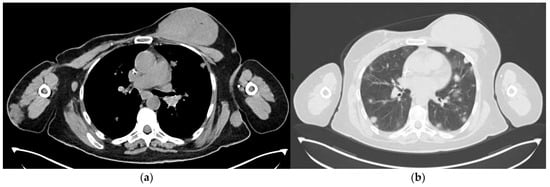

4.4. Computed Tomography